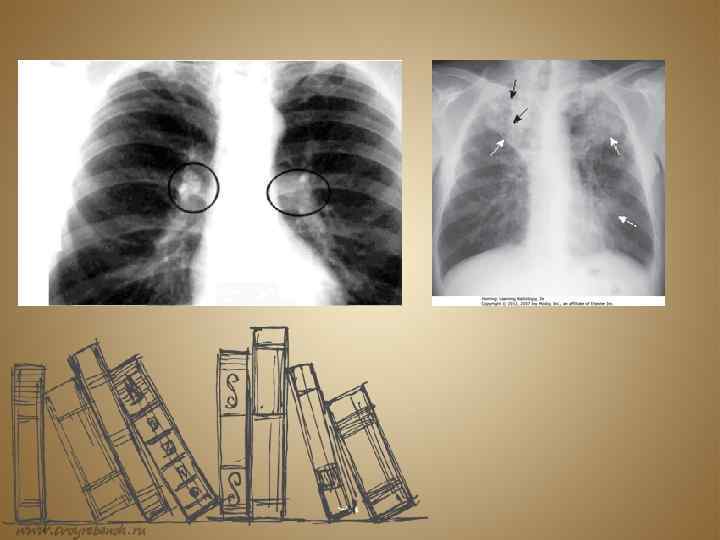

The classic symptoms of active TB infection are a chronic cough with blood-tinged sputum, fever, night sweats, and weight loss (the last of these giving rise to the formerly common term for the disease, "consumption"). Infection of other organs causes a wide range of symptoms. Diagnosis of active TB relies onradiology (commonly chest X-rays), as well as microscopic examination andmicrobiological culture of body fluids.